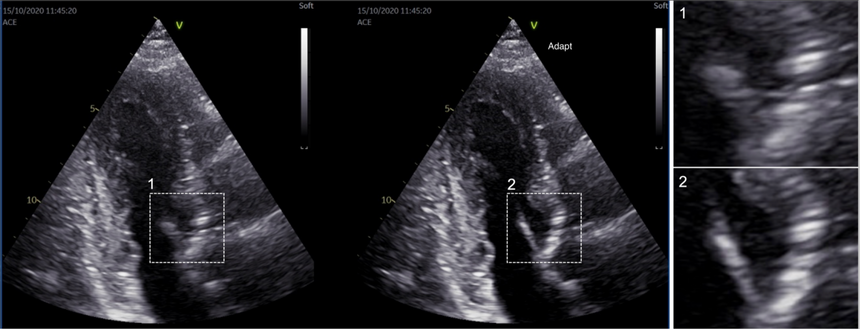

Venstre hjertekammer. Bildet til venstre er tatt uten Adapt på. Bildet til høyre er behandlet med cSound Adapt. Bildene er behandlet med nøyaktig de samme rådataene. Utsnittene 1 og 2 viser at hjerteklaff og hjertevegg kommer mye klarere frem med den nye teknologien. Foto:  SFI CIUS

– For eksempel blir hjerteklaffene tydeligere. Det gjelder også skillet mellom hjertemuskelen og hjertekammeret. Dette gjør det lettere å se strukturene i hjertet, noe som kan gi mer nøyaktige målinger og sikrere diagnostikk. Dette er viktig for å gi hver enkelt pasient best mulig behandling, sier Grenne.